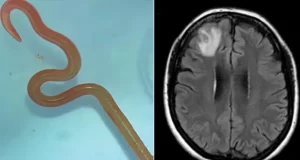

I liječnici u šoku: Nesretnoj ženi izvadili iz mozga živog crva dugog osam centimetara!

Ženi iz australske države Novi Južni Wales iz mozga je izvučen živ crv dužine osam centimetara nakon što je pune dvije godine patila od raznih zdravstvenih problema, priopćili su liječnici sa Odjela za infektivne bolesti u bolnici u Canberri. “Ophidascaris robertsi” je okrugli crv koji se obično nalazi kod pitona, koji je u njezino tijelo … Continue reading I liječnici u šoku: Nesretnoj ženi izvadili iz mozga živog crva dugog osam centimetara!